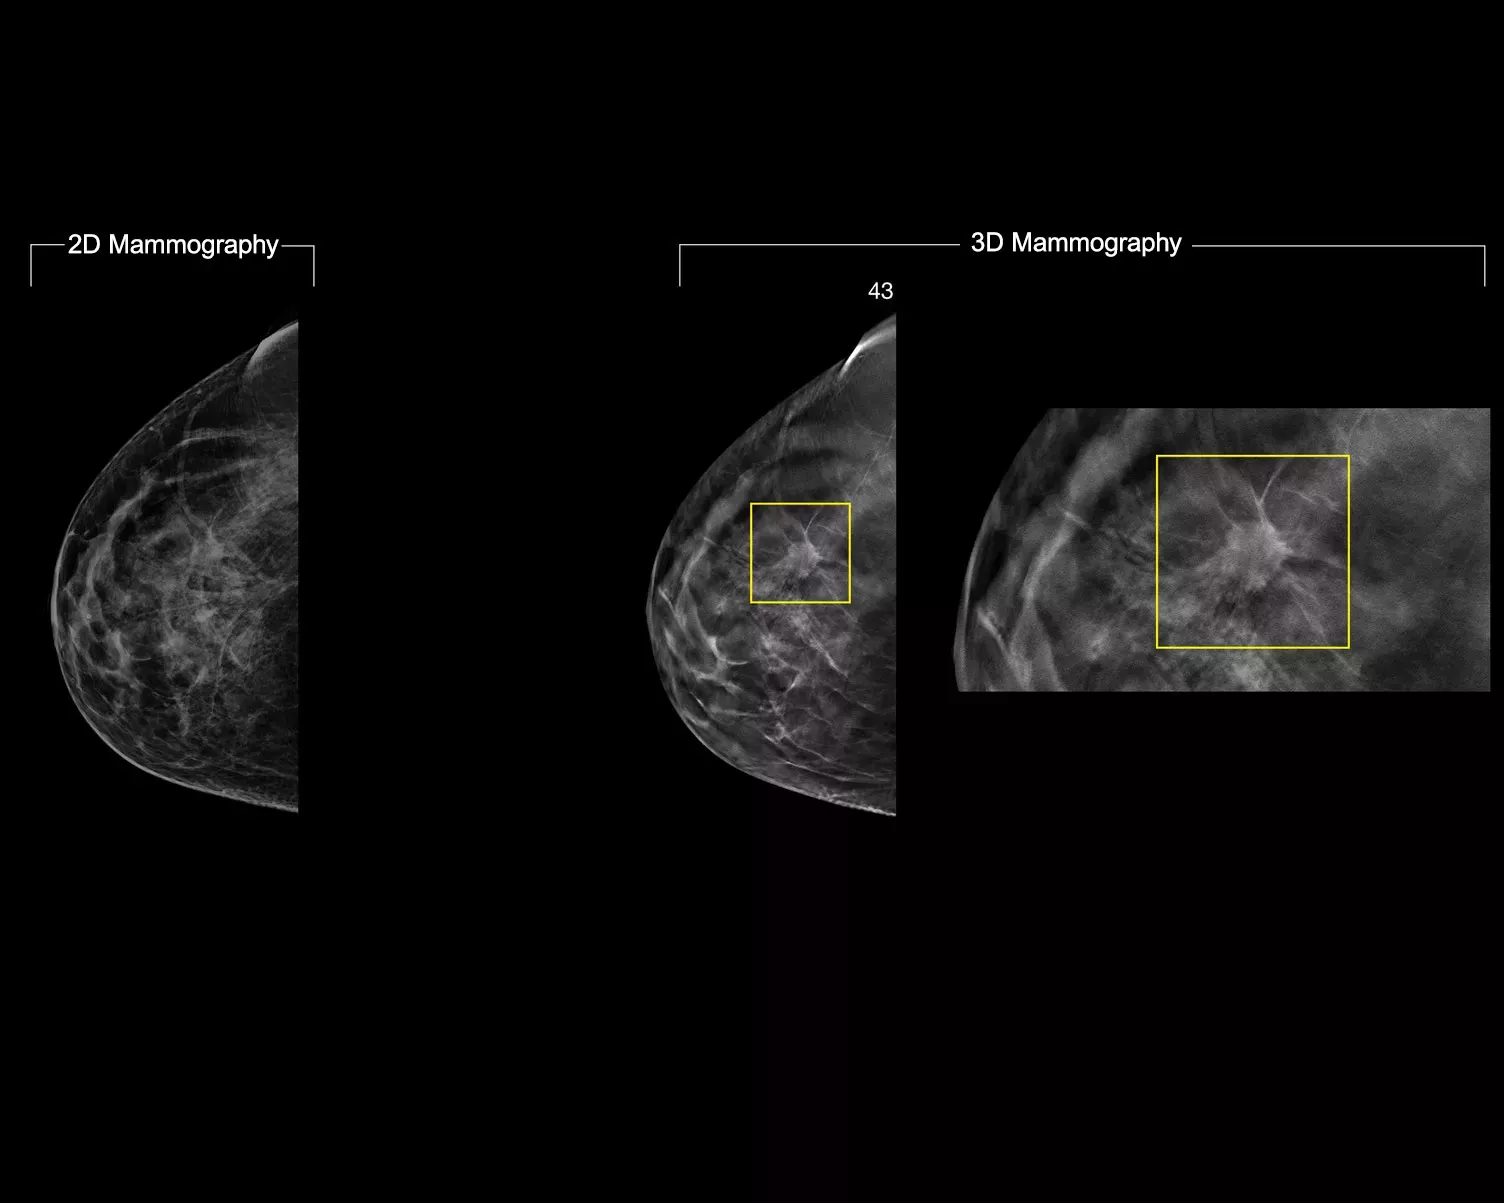

3DQuorum 技術により、Genius AI™ を活用した分析を利用して、高解像度 3D Mammography™ データを独自に再構築し、6 mm の SmartSlice を生成できます。画質、感度、正確性において妥協することなく、レビューする画像の数を減らすことで読影時間が短縮します2,3。当社の最新のイノベーションにより、読影時間を 1 日あたり 1 時間短縮できる可能性があります2,3*

3DQuorum イメージング技術 SmartSlice は、1 mm のトモシンセシス画像と同等の画質、感度、正確性で読影可能です。このソフトウェアは、SmartSlices の作成中に重要な特長を保持します2。3mmずつ重ねて生成された6mmスライスにより、スクロール時にデータ損失がなく、継続性が確保されます4-6

1 mm のスライスの代わりに SmartSlices を読影すると、レビューする 3D 画像の数が 3 分の 1 に減ります4-6。これにより、画像の解釈にかかる時間が 1 日平均 1 時間少なくてすみます3

3DQuorum テクノロジーは、Genius AI を活用した分析を利用して SmartSlices を生成し、レビューする画像の数を減らすことで読影時間を短縮します。画質、感度、正確性に妥協はありません4,5